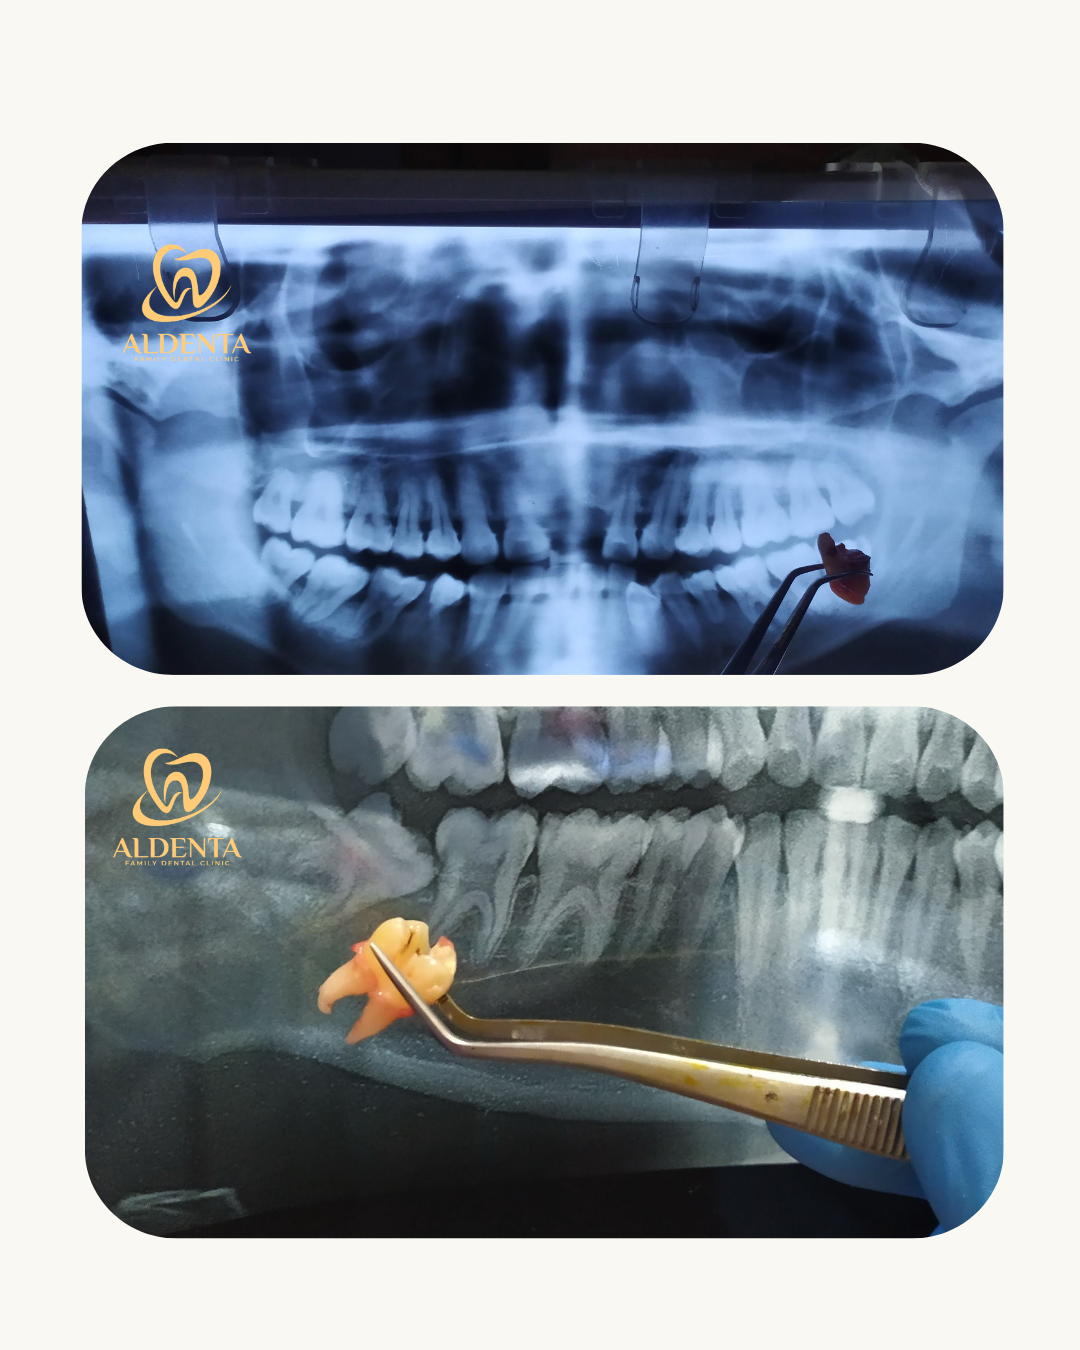

Odontektomi adalah tindakan bedah untuk mengangkat gigi yang tidak dapat dicabut dengan prosedur pencabutan biasa. Perawatan ini umumnya dilakukan pada gigi bungsu (wisdom tooth) yang tumbuh miring, terpendam di dalam gusi atau tulang, serta menyebabkan nyeri, bengkak, atau infeksi.

Prosedur odontektomi dilakukan oleh dokter gigi dengan anestesi lokal sehingga pasien tetap nyaman selama tindakan. Dokter akan membuka jaringan gusi secara hati-hati, kemudian mengangkat gigi yang terpendam. Pada beberapa kasus, gigi dapat dibagi menjadi beberapa bagian agar proses pengangkatan lebih aman dan minim trauma.

1. Pemeriksaan klinis dan rontgen untuk melihat posisi gigi.